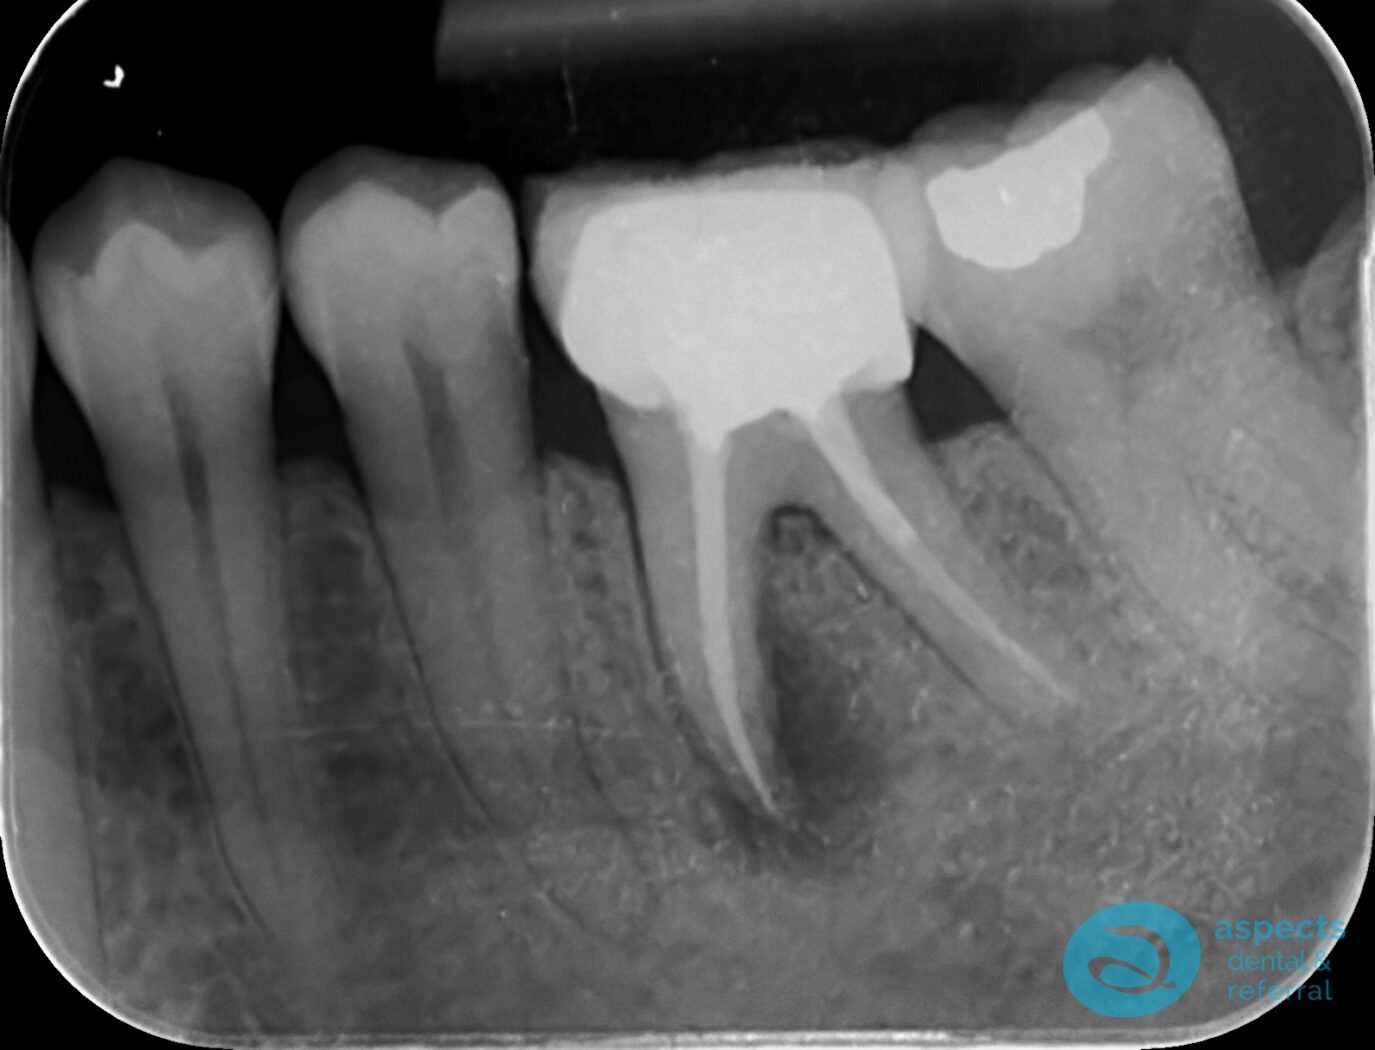

Our Dental Patient presented with a failing Root Canal-Treated Tooth with recurrent infection. Due to the persistent infection and poor prognosis, the tooth was extracted.

Before Tooth Extraction & Dental Implant Xray